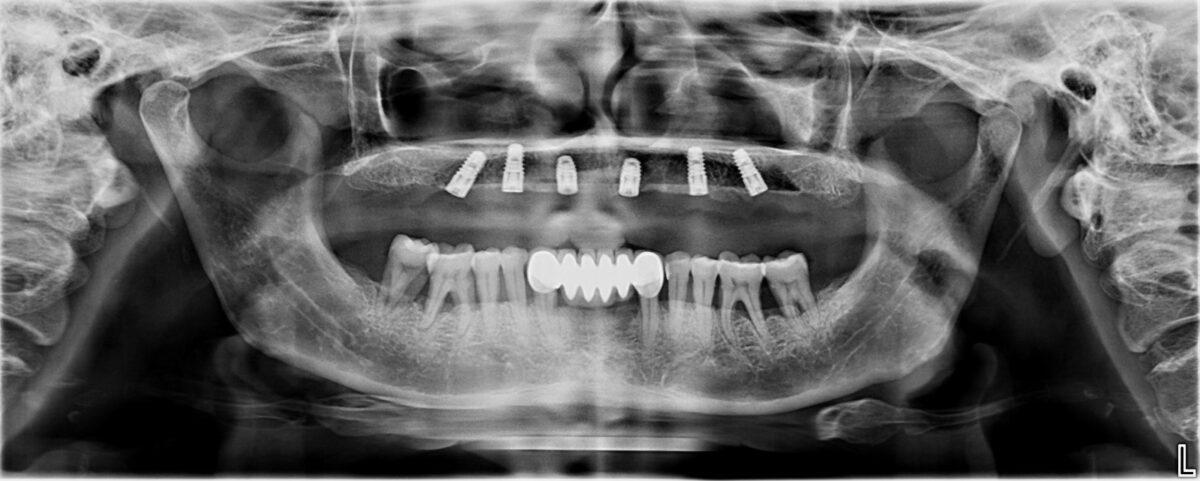

A dental implant is a titanium post placed into the jawbone to replace the root of a missing tooth. Once healed, it supports a crown, bridge, or denture, restoring natural function and aesthetics.

- Accurate diagnosis using digital imaging (CBCT scans)

- High-quality implant systems

- Proper surgical planning

Studio Dentale focuses on combining safety, precision, and aesthetics in every implant case.